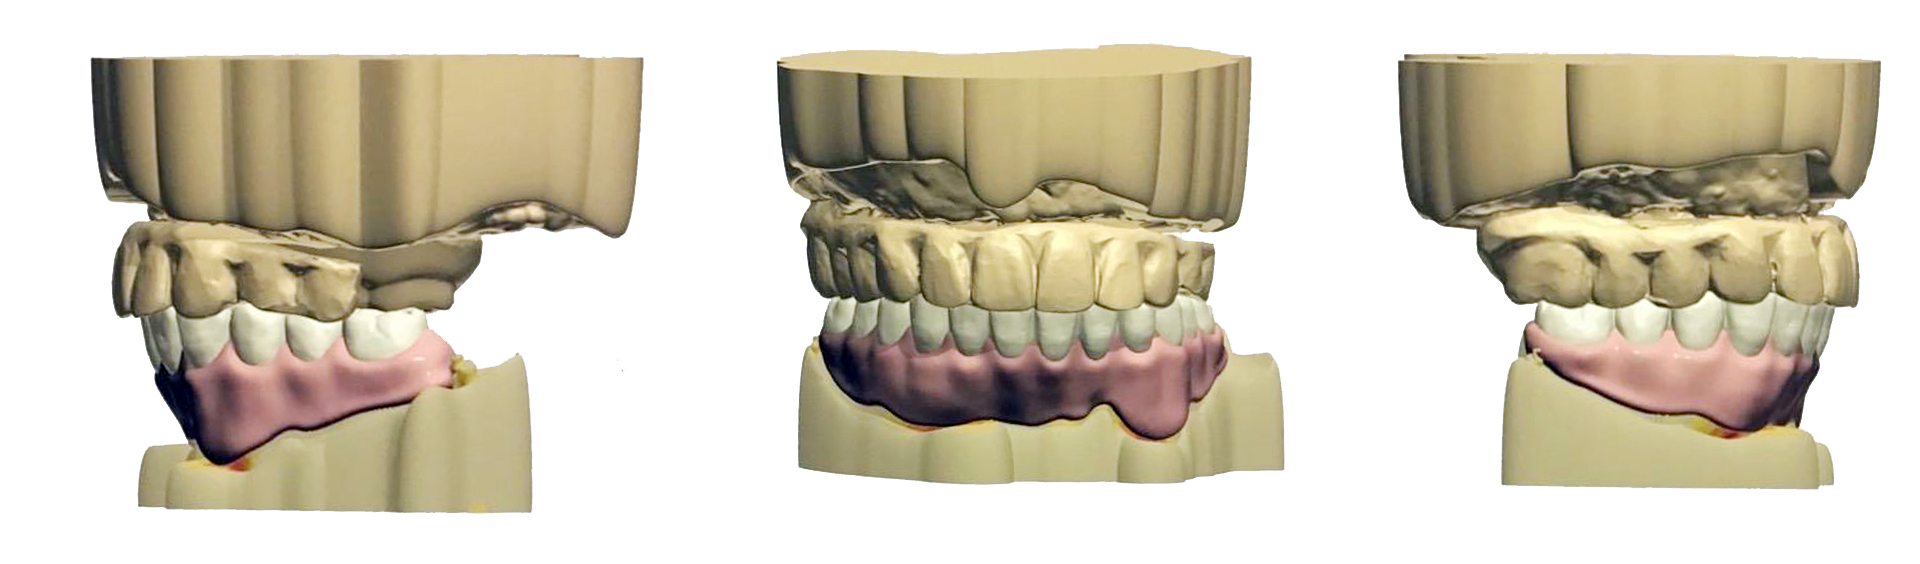

現在在術前規劃的部分,我們都會運用一些數位科技來協助,比方說用數位印模和3D電腦模擬,這樣我們可以更精確地設計您未來牙齒的位置和咬合情況,也能在治療前先把預計的效果模擬出來給您看。

▲數位排牙可更精確地設計您未來牙齒的位置和咬合情況

這樣您就可以很清楚知道手術後大概會是什麼樣子,有任何想調整的地方也可以事先討論,讓整個過程更安心、更有把握。